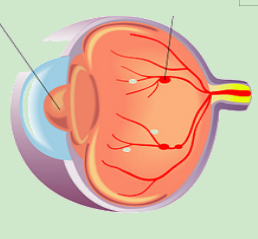

视网膜的小(xiǎo)血管長(cháng)期处于高糖环境中,变得脆弱,就像有(yǒu)裂缝的水管,容易渗漏、出血,从而引起视网膜的病变,可(kě)致视物(wù)模糊、黑影等,甚至失明。

糖网的视网膜血管渗漏